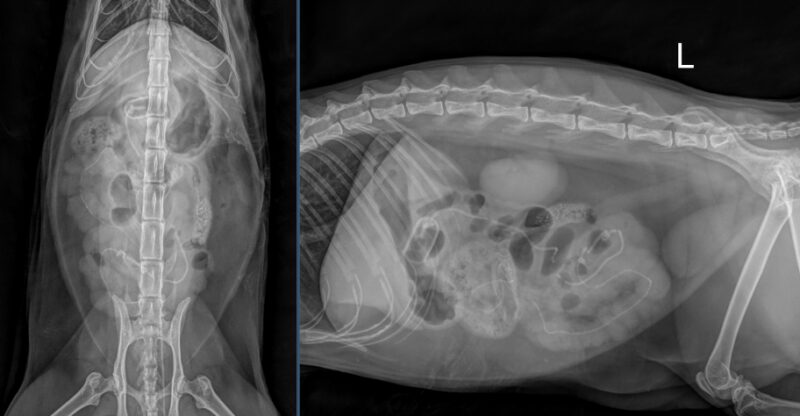

Liebe Kolleg:innen, vielen Dank für das Zusenden der Röntgenaufnahmen der Katze Bonita. In den vorliegenden dextro-sinistralen sowie ventro-dorsalen abdominalen Röntgenbildern zeigen sich mehrere auffällige Veränderungen im Bereich des Magen-Darm-Trakts. Auf Höhe des Übergangs von Pylorus zu proximalen Duodenum ist eine ovoide Struktur mit mineraldichtem peripherem Saum erkennbar, die zu einer mechanischen luminalen Einengung in diesem Bereich führt (erste grün gepunktete Kreise). Ausgehend von dieser Struktur projiziert sich ein lineares, röntgendichtes Material innerhalb des gesamten Dünndarms, wodurch es zu einer markanten Auffädelung mehrerer jejunaler Darmabschnitte kommt (grüne Pfeilköpfe). Eine weitere ähnlich ovale röntgendichte Struktur befindet sich innerhalb des Jejunums, die eine zusätzliche mechanische Obstruktion verursacht (zweite grün gepunktete Kreise). Es bestehen innerhalb des gastrointestinalen Trakts multifokale Gasblasen, die von weichteildichtem Darminhalt umgeben sind. Das fadenförmige Fremdmaterial endet auf Höhe des Colon descendens in einer kotähnlichen Formation (pinker Pfeilkopf). Aborad dieser Struktur stellt sich das restliche Colon leer dar.

Der Magen ist zusätzlich leicht bis moderat Gas gefüllt. Es besteht kein Hinweis auf freie Flüssigkeit oder freies Gas innerhalb der Peritonealhöhle. Die Leber stellt sich spitzrandig und gut abgrenzbar dar. Milz, Nieren sowie die Harnblase sind ohne besonderen Befund. Im ventralen Anteil des Abdomens ist in der seitlichen Projektion ein Artefakt erkennbar, sehr wahrscheinlich bedingt durch Ultraschallgel des zuvor durchgeführten A-FASTs (grüner gepunkteter Quadrant), welches somit als nicht pathologisch zu bewerten ist. Zudem besteht intraabdominal ein deutlicher Anteil an fettdichter Verschattung. Der abgebildete Bewegungsapparat ist unauffällig.

Zusammenfassend ist von einem mechanischen Ileus auszugehen, verursacht durch röntgendichtes Fremdmaterial im Bereich des Pylorus/proximalen Duodenums sowie des Jejunums. Zusätzlich befindet sich ein linearer Fremdkörper innerhalb des Dünndarms, der zu einer Auffädelung multipler Dünndarmschlingen führt, derzeitig ohne Hinweis auf Perforation. Es besteht jedoch ein erhebliches Risiko für Strangulation, Ischämie und Darmperforation, womit es sich hierbei um einen chirurgischen Notfall handelt und dringend zu einer zeitnahen operativen Versorgung geraten wird.